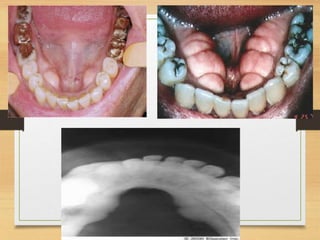

Clinical features:

• Any age, common in teenagers and young adults(10 and 19).

• Female predilection.

• Well-demarcated focal nodular mass exclusively on gingiva

(originate from interdental papilla).

•Maxillary arch : incisor-cuspid region.

•Teeth are unaffected, rarely migration and loosening of teeth.

•Sessile or pedunculated base.

•Begin as red ulcerated lesion

•Older ones - Pink non ulcerated

•Color ranges from red to pink , surface is frequently but not

always ulcerated.

• The growth begins as an ulcerated lesion, older ones

are more likely to demonstrate healing of the ulcer

and an intact surface.

• Red ulcerated ones are mistaken for pyogenic

granulomas

• Pink nonulcerated ones are similar to irritation

fibromas.

• Less than 2cm.

• Lesion may be present for many weeks or months

before diagnosis.